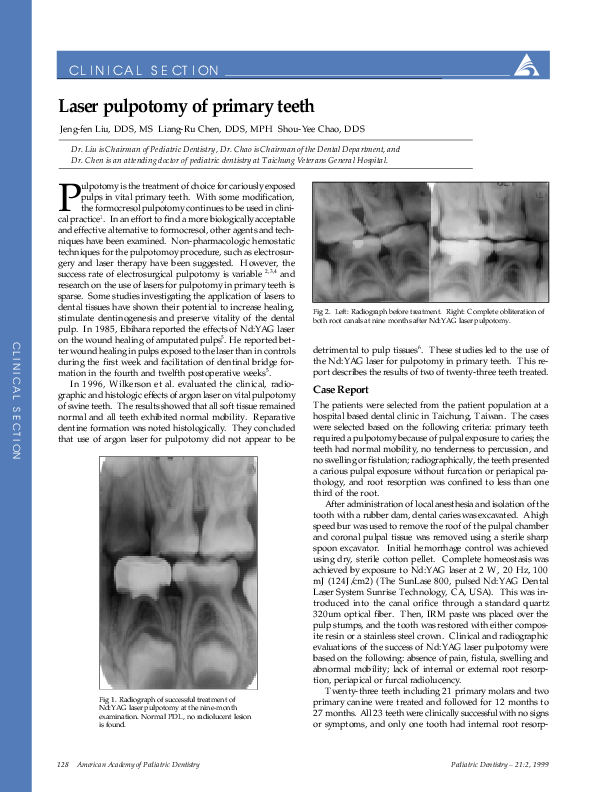

(PDF) Laser pulpotomy of primary teeth Surabhi Bhardwaj Academia.edu Pulpotomy Procedure Pdf a pulpotomy is performed in a primary tooth with extensive caries but without evidence of radicular pathology when caries removal. this paper provides an overview of the pulpotomy procedure in primary teeth over a century, with reference to advances in technique, medication. 2.3 pulpotomy a pulpotomy entails the removal of the coronal pulp and maintenance of the. Pulpotomy Procedure Pdf.